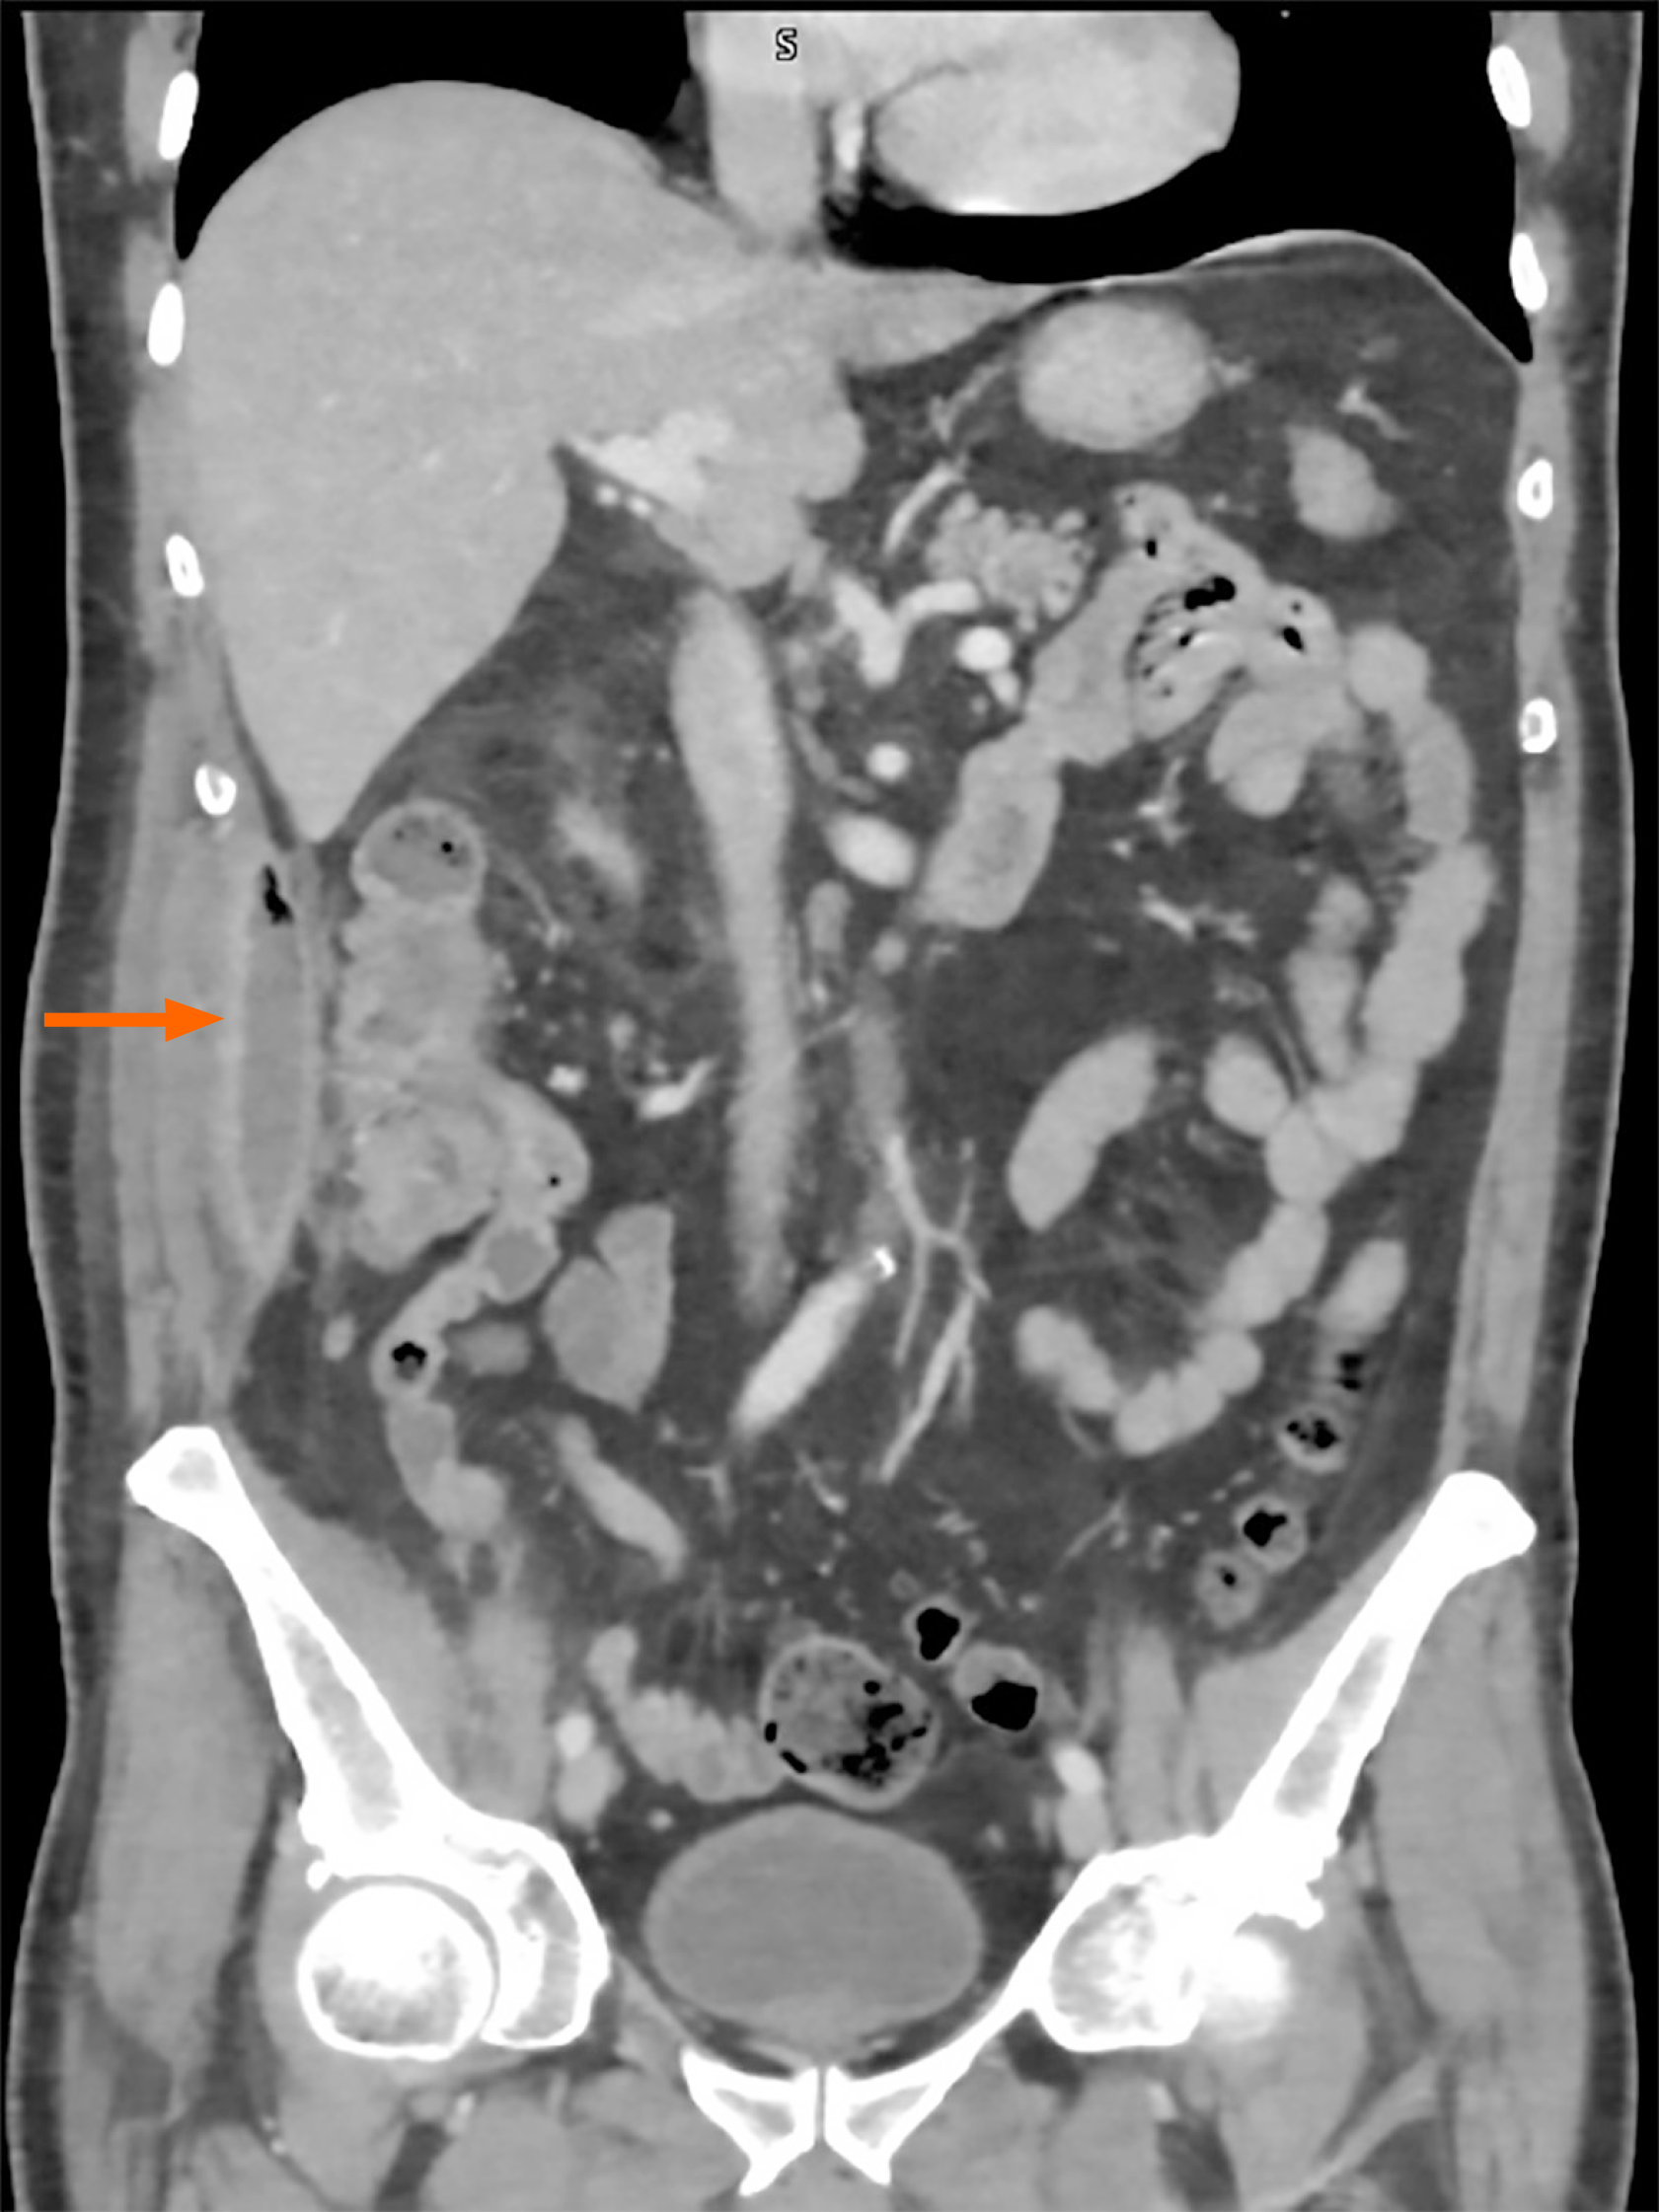

Figure 3 Abdominal computed tomography scan image.

The abscess collection adjacent to the right colon is indicated by the arrow.